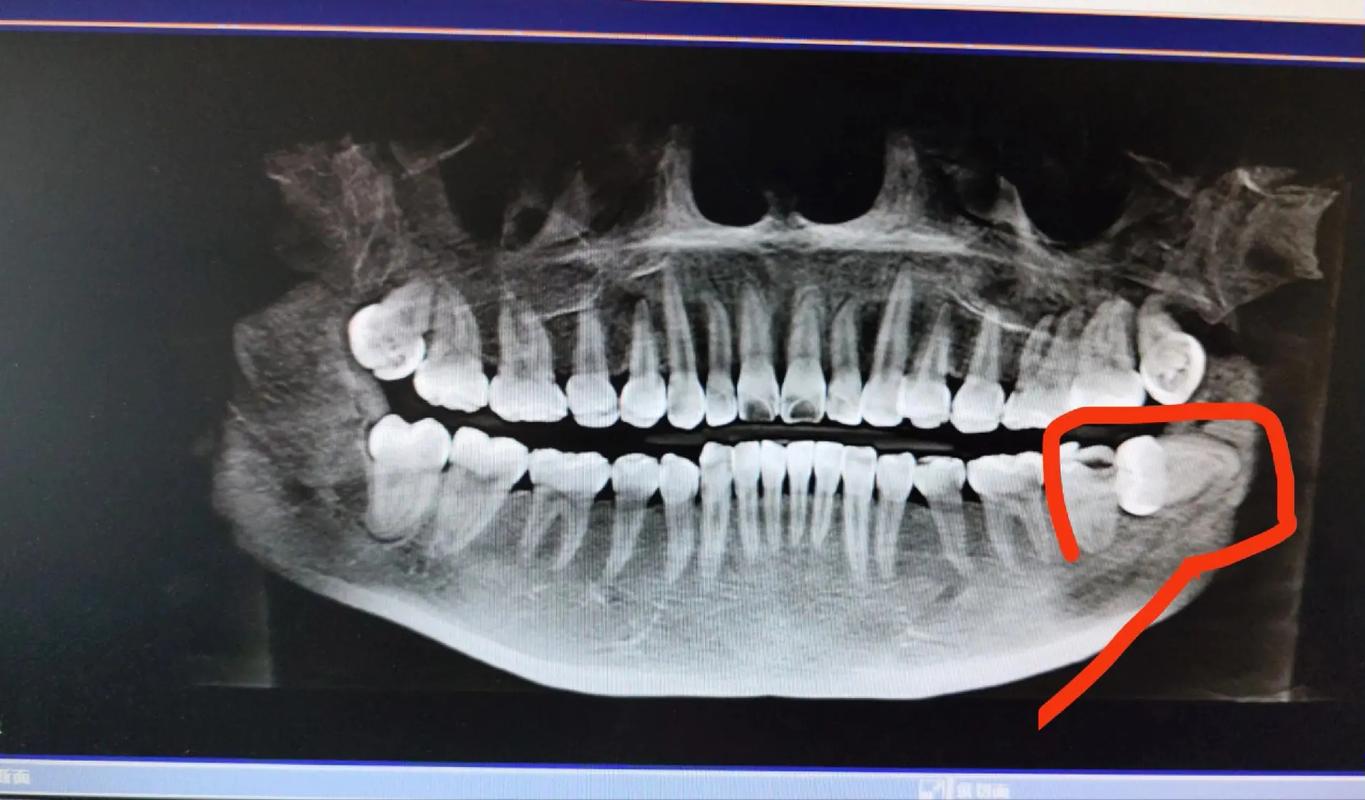

- X光片监测的重要性:曲面断层片或CBCT(锥形束CT)是评估未萌智齿的“金标准”,可清晰显示智齿位置、方向、与邻牙关系及骨内情况,医生需根据影像结果判断风险。